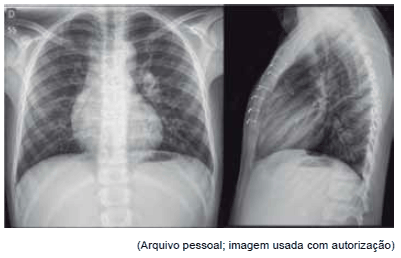

Paciente de 16 anos foi encaminhada ao Pronto-Socorro com quadro de dor torácica, palpitações e palidez cutânea associadas. Ao exame físico, notou-se semiologia cardiovascular normal, porém com ausculta das bulhas em hemitórax direito. Foram solicitados os seguintes exames:

O diagnóstico mais provável é:

Observe as seguintes figuras.

Elas são compatíveis com qual diagnóstico?